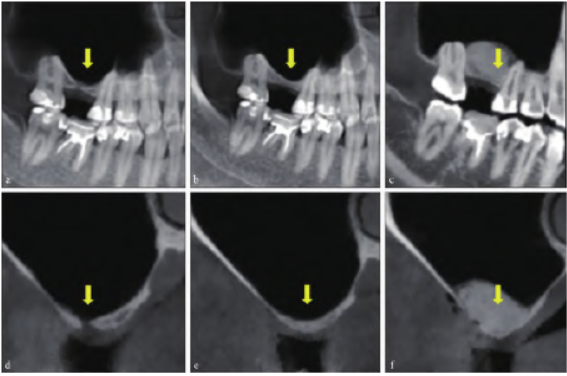

颌面部锥形束CT (cone beam computed tomography,CBCT) 示双侧髁突未见异常。16 牙牙槽骨高度2 mm,宽度7 mm。右侧上颌窦内影像均匀,窦底处骨板影像不连续且与16 牙牙槽嵴顶相通,形成3 mm×2 mm×2 mm类圆形低密度缺损区(图2a、d)。

海绵至窦底处,于牙槽嵴顶表面覆盖Bio-Gide 胶原膜(Geistlich 公司,瑞士)(图1d~f)。术后3 个月CBCT 示上颌窦底完整、有连续性,窦嵴距2 mm(图2b、e)。

3 个月后行上颌窦外提升术:小范围开窗,充分完整剥离,捏鼻鼓气试验呈阴性,将Bio-Gide胶原膜的一部分置入窦底处用以保护反复穿通的黏膜,植入Bio-oss 骨粉(Geistlich 公司,瑞士)后,将另一部分暴露于外侧壁的Bio-Gide 胶原膜于颊侧反折后膜钉固定(图1g~i)。术后10 个月CBCT 示16 牙术区窦底内可见高密度影像,成骨良好,可用骨高度约11 mm(图2c、f)。

图 2 患者CBCT。a:矢状面观术前;b:矢状面观第一次手术后;c:矢状面观第二次手术后;d:冠状面观术前;e:冠状面观第一次手术后;f:冠状面观第二次手术后。箭头示上颌窦底。